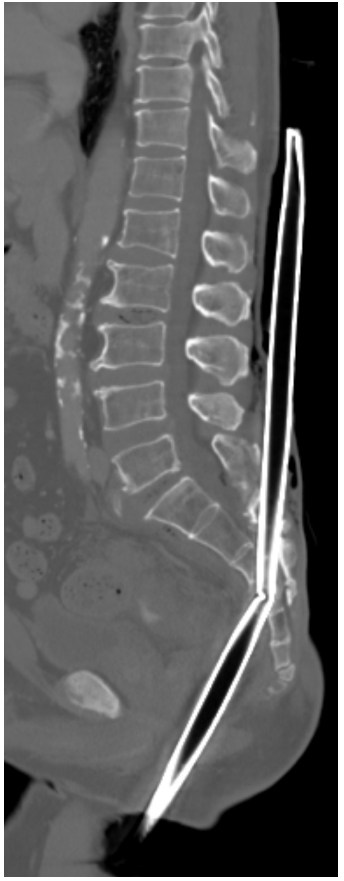

A Big Runner Gallery A Big Runner By Nicole Angemi|2025-05-21T09:34:16-04:00October 7th, 2023|MEDICAL, Transportation, Anatomy, The Gross Room| Read More 41